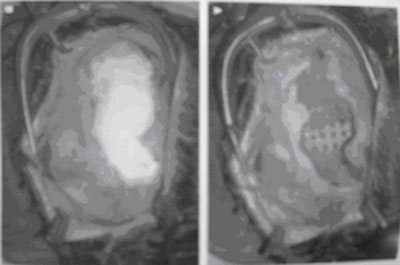

脑部CT扫描 主要是观察软组织的受累情况,以及周围软组织条件,重要肌肉,血管神经的比邻关系

头颅3维CT扫描 可以了解复杂的解剖关系,而且可以用所得到的数据进行个性化修复体的制作。

图5 头颅冠状位CT

(来自plastic and reconstructive surgery)

图7 三维重建CT

(图片来自于病案收藏)